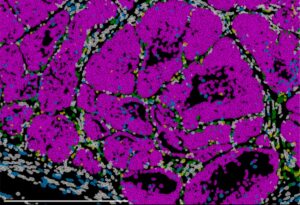

El ensayo clínico de fase 2 SUNNIFORESCAST demuestran que la combinación de ipilimumab y nivolumab mejora la supervivencia a 12 meses de pacientes con carcinoma